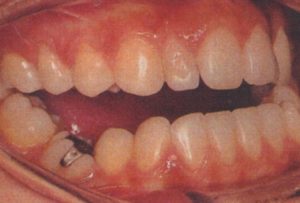

萌出したばかりの前歯が逆被蓋になってしまった場合、できれば早い時期に正しい被蓋にするのの越したことはありません。

また、この時期にクロスバイトになっているようなケースも同様です。

早期治療によって前歯部の被蓋が改善しても、残念ながら思春期の成長のスパート時に下顎骨が大きくなり、

小学校高学年から中学校にかけて再び被蓋が逆転してしまうことがしばしばあります。

一般的に反対咬合の本格的治療は、下顎骨の成長発育がある程度見通しがついてから始めるべきでしょう。